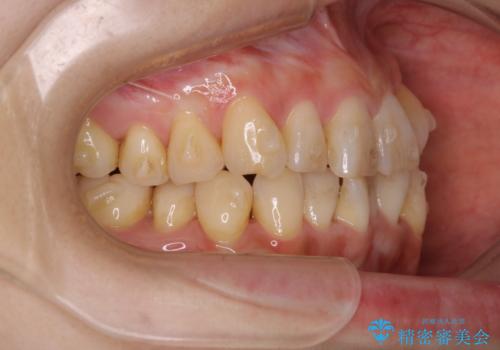

インビザラインでのマウスピース矯正中に歯を白くしたい

- インビザラインでのマウスピース矯正中に、歯の黄ばみが気になるため綺麗に白くしたいとのことでした。PMTC60分コースを行いました。

PMTC(保険外治療)は、毎日の歯磨きで落としきれない汚れや、コーヒ、紅茶・タバコのヤニなどの着色も除去します。目には見えない歯と歯の間・歯肉の境目・インビザライン中はアタッチメント周囲などに残っているプラーク(歯垢)もしっかり取り除きます。PMTCでは専門的な機械や材料を使用して、徹底的に汚れを除去するため、虫歯・歯周病・口臭予防などにつながります。